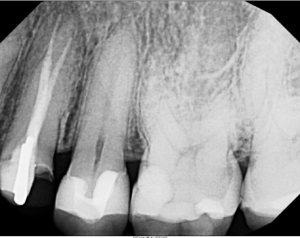

This video demonstrates alveolar ridge preservation following atraumatic surgical extraction of an endodontically treated tooth. Emphasis is placed on minimizing surgical trauma to preserve existing hard and soft tissues.

The case features flap management in the presence of a buccal dehiscence, followed by bone graft placement and stabilization using a dense polytetrafluoroethylene (d-PTFE) membrane. Surgical principles, membrane selection, and handling techniques are discussed to optimize ridge dimensions and facilitate future implant placement.